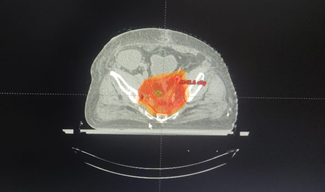

Postop histopathology of liver showing moderately differentiated hepatocellular carcinoma and Rectum showing moderately differentiated adenocarcinoma of rectum with free margins and free regional lymph nodes with perirectal tumor deposits pT3N1c. He received adjuvant external beam radiotherapy in view of T3 and node positive using Image guide radiotherapy (IGRT) to a dose of 45 Gy in 25 fractions to the post op bed and nodes in pelvis followed by 5.4 Gy in 3 fractions boost to the post-operative bed as shown in Figure 3 along with concurrent chemotherapy with oral capecitabine The patient received stereotactic body radiotherapy(SBRT) using CyberKnife to a dose of 30 Gy in 5 fractions to postop bed of liver using gold fiducial and synchrony respiratory tracking as shown in Figure 4. SBRT to liver considered in view of close margin 2mm.now on one and half year follow up whole body PET scan as shown in Figure 5 revealed no active disease and patient have a good quality of life.

Figure 4 SBRT plan for liver lesion.